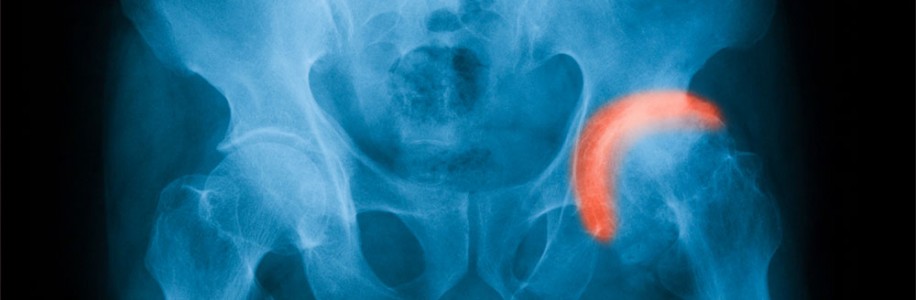

ΟΣΤΕΟΑΡΘΡΙΤΙΔΑ ΙΣΧIΟΥ

Η αρθρίτιδα του ισχίου είναι μια εκφυλιστική νόσος, που προκαλεί πόνο και μείωση της κινητικότητας της άρθρωσης, δημιουργώντας σημαντικού βαθμού αναπηρία με ανάλογες συνέπειες στην ποιότητα ζωής των ασθενών. Όταν η φαρμακευτική αγωγή δεν επαρκεί, τότε η χειρουργική αντιμετώπιση της νόσου είναι η καλύτερη λύση. Σήμερα υπάρχουν τρόποι αντιμετώπισης ανάλογα με τις ιδιαιτερότητες και τις ανάγκες του κάθε ασθενούς, οι οποίοι έχουν θεαματικά αποτελέσματα.